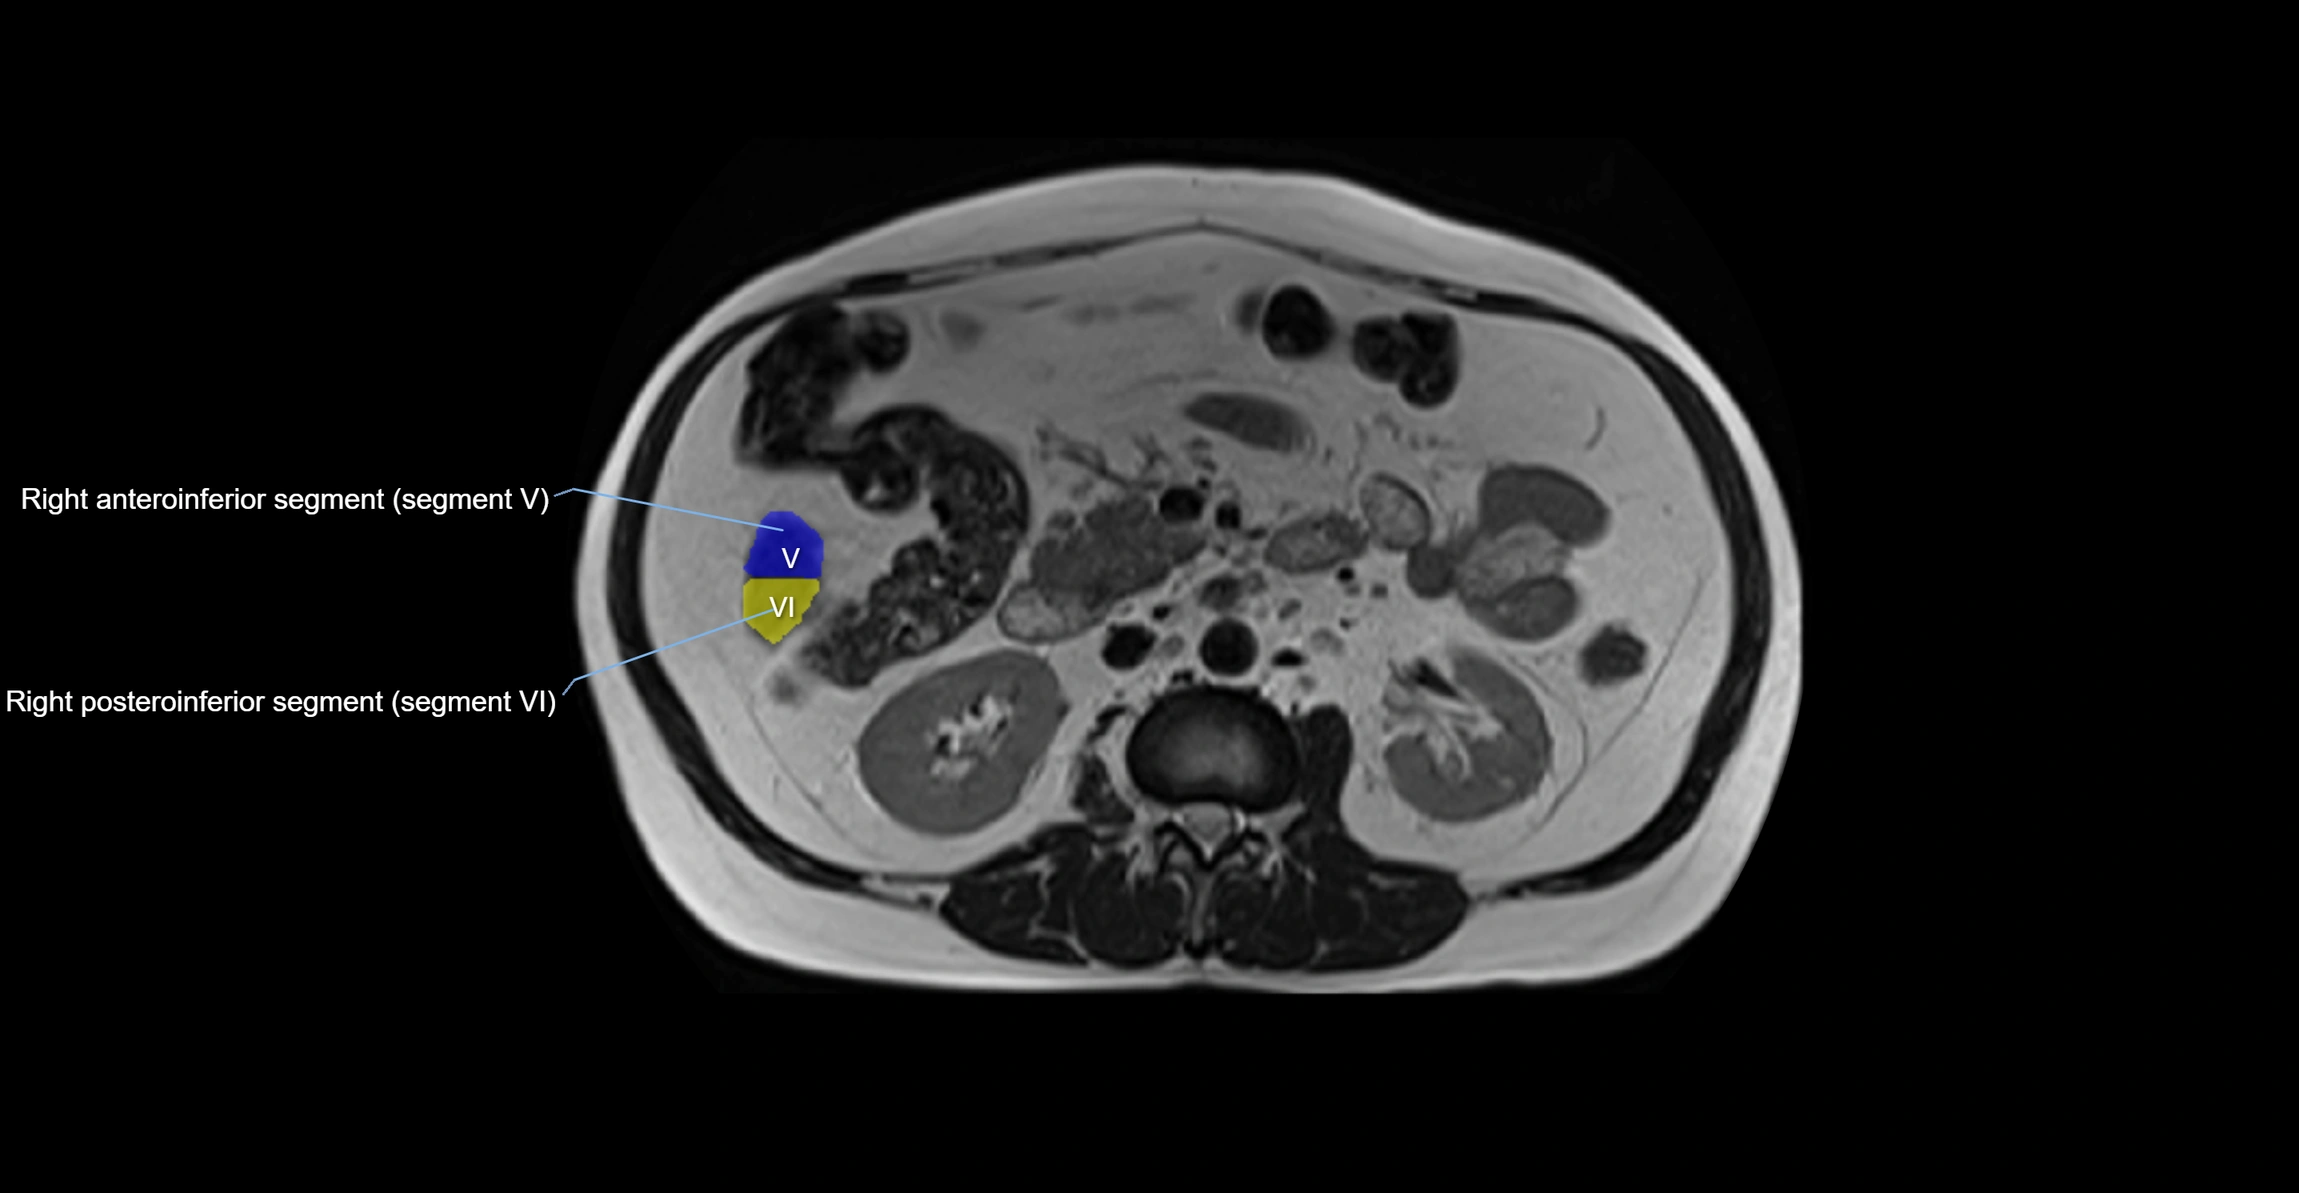

MRI image

image